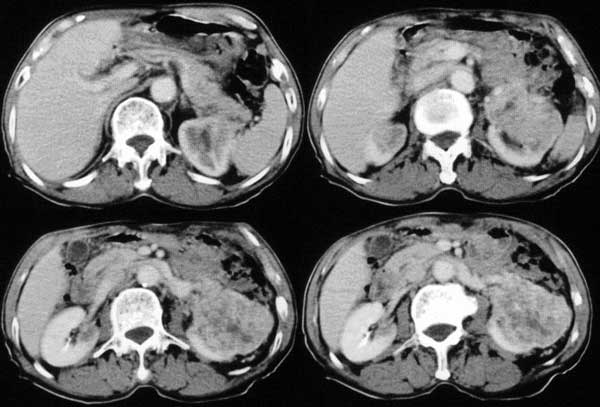

附肾脏平扫及增强片

手术是怎么做的,好像没做。右肾还有两个病灶。气管腔内的那个结节密度确实很低,考虑粘痰核应该没问题,若是新生物不会这么低。不过挂在前壁上了,少见!

肺及胸膜下多发结节影,胸椎及附件、肋骨破坏支持转移癌。气管内结节影支持痰核。肾脏ct应该是术前的吧?左肾内亦见一低密度灶,另外胰腺好像也不规则。不知术后结果如何?

左侧肾癌,腹膜后淋巴转移,肺及胸椎转移,右肾转移可能,气管内痰栓可能[壁可见]

左侧肾癌伴腹膜后淋巴结、胸椎、双肺内转移。